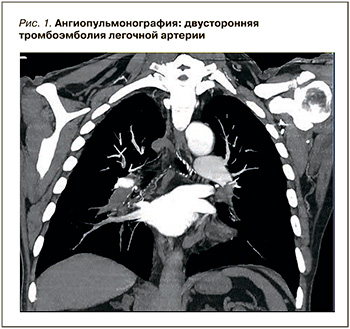

Для верификации данного предположения была проведена компьютерная ангиопульмонография, позволившая обнаружить признаки двусторонней ТЭЛА на уровне сегментарных ветвей и наличие тромбов в обоих предсердия (рис. 1).

Для верификации данного предположения была проведена компьютерная ангиопульмонография, позволившая обнаружить признаки двусторонней ТЭЛА на уровне сегментарных ветвей и наличие тромбов в обоих предсердия (рис. 1).